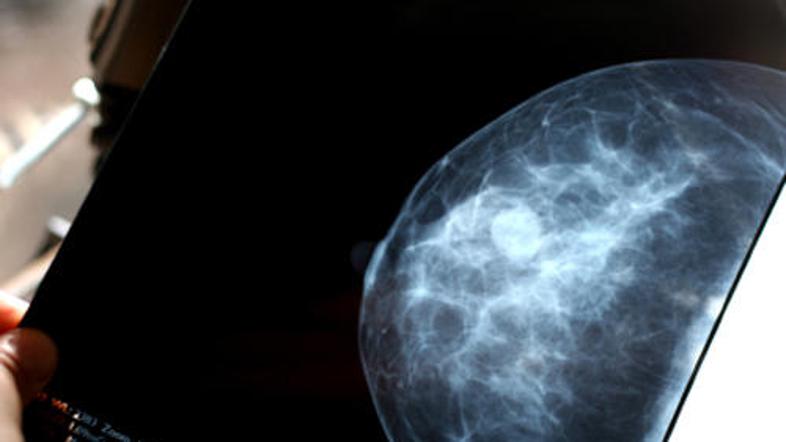

V eni izmed britanskih bolnišnic so "pozabili" obvestiti ženske, pri katerih so odkrili raka na dojkah. Bolnišnica je že uvedla preiskavo zoper enega izmed radiologov.

Potem ko se je eni izmed pacientk zazdelo, da je nenavadno, da mamografija ni pokazala ničesar, čeprav je jasno otipala zatrdlino, so v bolnišnici Accrington Victoria Hospital še enkrat pregledali njene posnetke. Ti so jasno kazali, da ima ženska raka, ki je celo zelo napredoval.

Pregledali so vse radiološke posnetke za tri leta nazaj in ugotovili, da bi moral radiolog, ki jih je napravil, na dodatne preiskave poklicati kar 85 žensk, poroča Sky News.